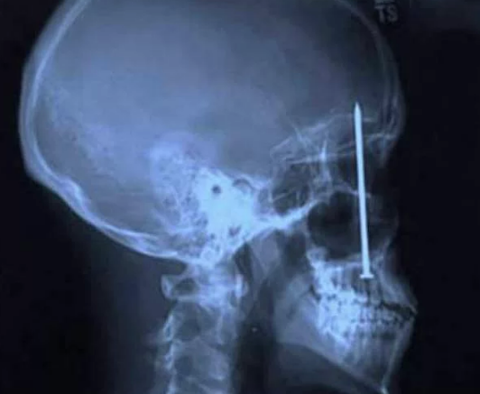

Galerinin tamamı için tıklayınızDiş Ağrısından Fazlası

Bu Xray'in sahibinin o çiviyi oraya sokmasından daha ilginci, diş

ağrısı sebebiyle dişçiye gittikten sonra orada bir çivinin olduğunu

farketmesi..